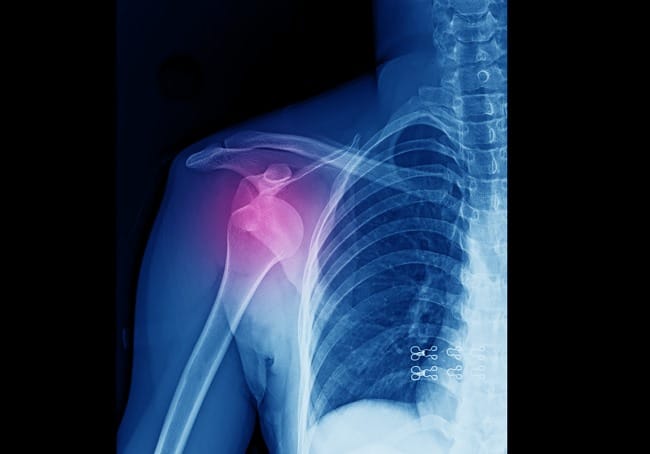

Dokter akan menanyakan gejala yang dialami dan kejadian yang menyebabkan tulang lengan atas terlepas, kemudian melakukan pemeriksaan fisik. Setelah itu, dokter juga akan melakukan pemeriksaan foto Rontgen pada bahu pasien, untuk melihat seberapa jauh sendi bahu terlepas dan mendeteksi kerusakan pada jaringan di sekitarnya.